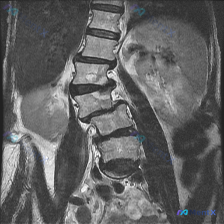

核心影像表现(腰椎MRI T2冠状位):

- 腰椎序列左侧弯畸形,椎体排列基本连续

- L2/3、L3/4、L4/5椎间隙不对称性变窄(左侧更甚)

- 多节段椎间盘T2弥漫性低信号,提示脱水、变性

- 侧弯凹侧小关节信号及结构紊乱

- 双侧髂嵴高度不对称,两侧腰部软组织不对称

- 未见明显骨质破坏、边界不清的软组织肿块或椎旁脓肿